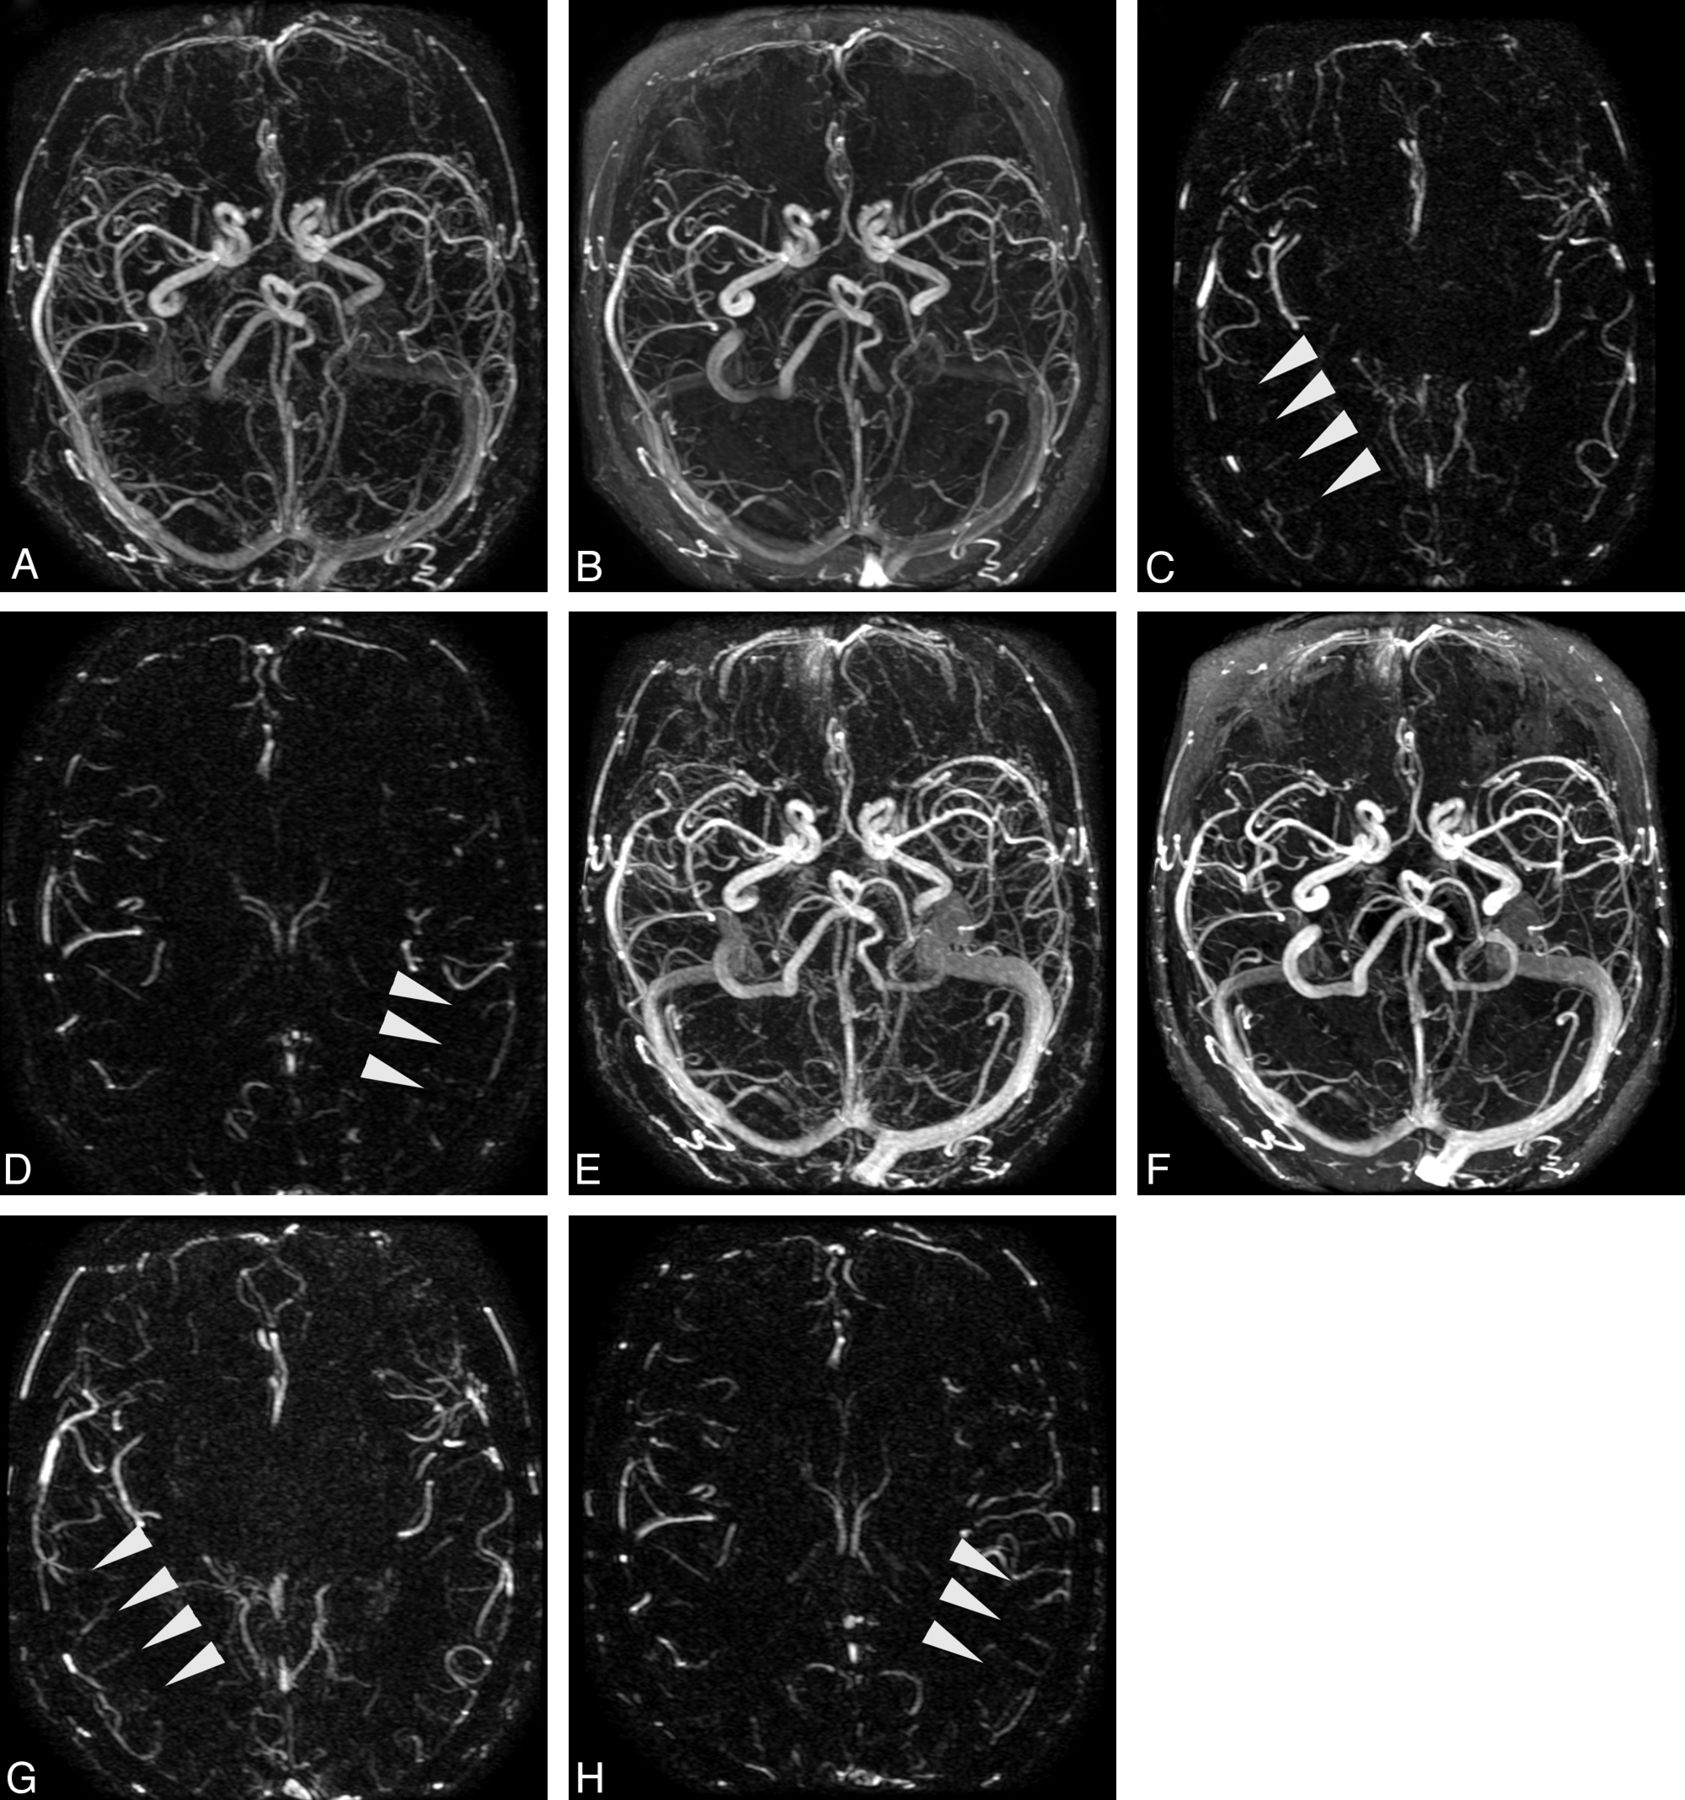

Patient (71-year-old man) undergoing successive TR-MRA, spaced approximately 1 year apart, for evaluation of previously coiled left ophthalmic artery aneurysm. Images obtained after injection of SCA (A–D) and obtained with BPA (E–H). Background-subtracted (A and E) and unsubtracted (B and F) axial MIP volumes from SCA and BPA TR-MRA, respectively; C,G,D, and H are background-subtracted axial source MRA images from peak arterial phases derived from SCA (phase 7) and BPA (phase 9) examinations. Note the improved demonstration of mid and distal MCA branches in both hemispheres with administration of the blood-pool agent.

BPA angiograms were of generally greater quality across all interrogated vascular segments (Table 2), with average rating compared with SCA on unsubtracted volumes as follows: ICA = 2.88 ± 0.33 versus 2.56 ± 0.61, P = .002; M2 = 2.62 ± 0.57 versus 2.24 ± 0.69, P = .003; M3 = 2.44 ± 0.58 versus 1.76 ± 0.92, P < .001 (Fig 2). A trend toward superiority of BPA, not reaching statistical significance, was observed for the M1 segment of the MCA: 2.8 ± 0.45 versus 2.62 ± 0.49, P = .059; subtracted volumes similarly showed significantly improved quality on BPA angiograms for most segments.